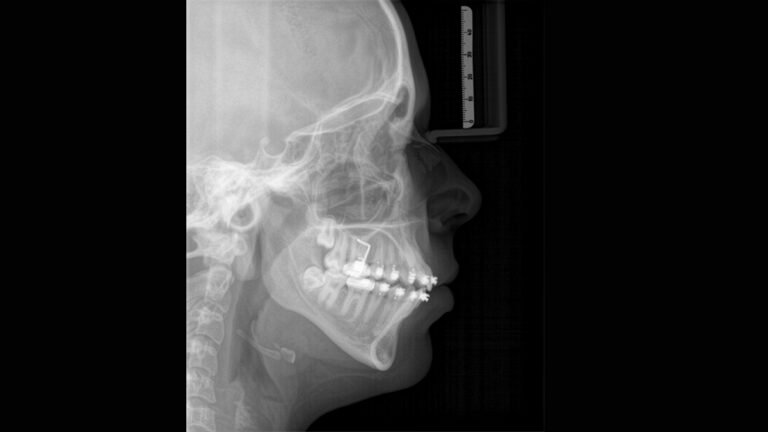

すべての矯正ニーズをカバーするセファロプログラム

専用のセンサーを使用して、横向き、左右対称のp.a.p.やa.p.だけでなく、手根骨の画像も取得できます。歯の位置がずれている場合は、3Dレントゲンで正確な位置を確認することもできます。